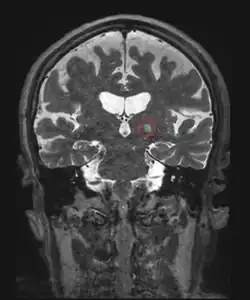

Another invasive surgical treatment of essential tremor is deep brain stimulation (DBS). DBS is a surgical procedure that involves the placement of a permanent electrode with 4-8 contacts within the brain with connecting wires connected to a pulse stimulator implanted near the patient's collarbone.[65] In the treatment of tremor, the electrodes are placed in the ventral intermediate nucleus (Vim) of the thalamus.